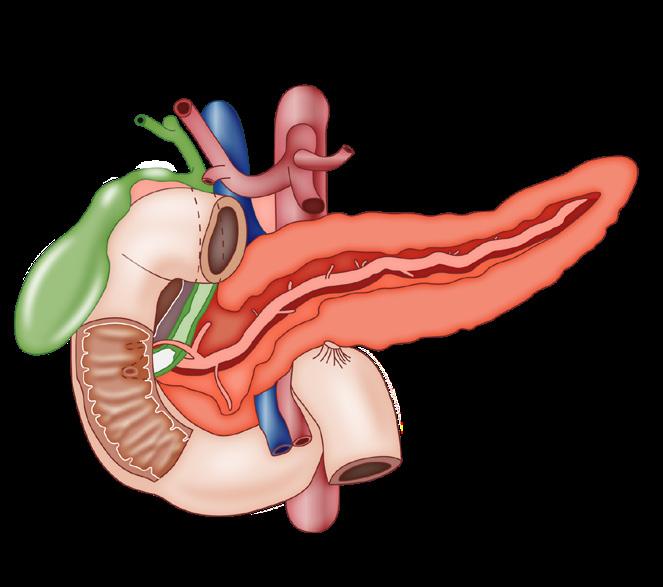

Figura 29. Fármacos que bloquean al sistema renina angiotensina: DRI: inhibidores directos de la renina como aliskirem, ACE-I: inhibidores de la enzima convertidora de angiotensina como captopril o enalapril, ARB: bloqueadores de los receptores de angiotensina II como valsartán o losartán.